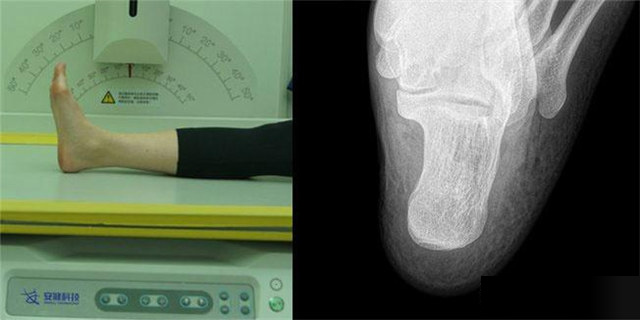

下肢:脛腓骨、踝、足脛腓骨長骨檢查需要包括--側的關節踝關節常規正+外側位,特殊時可選內斜位足常規前后正位+內斜位,外傷鑒定等情況,需要負重的水平側位(包括足尖和足跟)跟骨側位+軸位